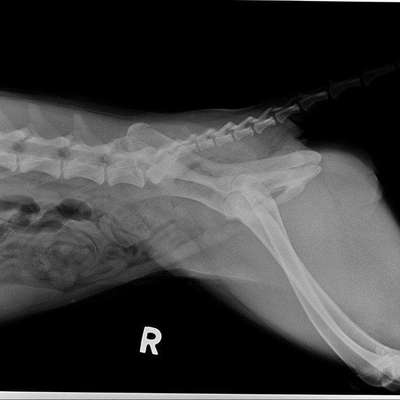

Hallo🙋🏻‍♀️ Wir haben im Mai einen Welpen aus Rumänien adoptiert. Sie war immer schon sehr hüpfend beim laufen und sehr gelenkig. Nun hatte sie vor einem Monat Schmerzen nach kurzem toben, weshalb wir gleich zum Arzt sind. Es gab Schmerzmittel und wir sollten das weiter beobachten. Als es wieder kam, sind wir direkt wieder zum Arzt und haben für letzte Woche einen Termin zum röntgen bekommen. Diagnose: Schwere HD. Unsere Ärztin hat uns Zusätze und Physio empfohlen und gab uns Hoffnung, dass das vllt wieder werden könnte, da sie erst ca.10 Monate alt ist. Hab hier jemanden Erfahrung damit? Tipps? Wir wohnen in der Nähe von Bielefeld und überlegen ob wir uns in einer Klinik bezüglich einer Operation beraten lassen sollten, da wären wir über Erfahrungen ebenfalls sehr dankbar 🙏🏻 Wichtig wäre, dass wir eine OP auf Raten zahlen können!

Das sieht im Röntgenbild echt übel aus.

Unser Labbi Benny hat auch HD, ein kleines bisschen weniger schlimm als Ylvie.